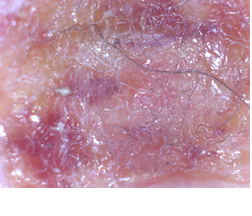

Several months following the tick bite, Wysocki began to experience symptoms such as fatigue, power loss in his shots, and rashes. A blood test confirmed his Lyme disease diagnosis.